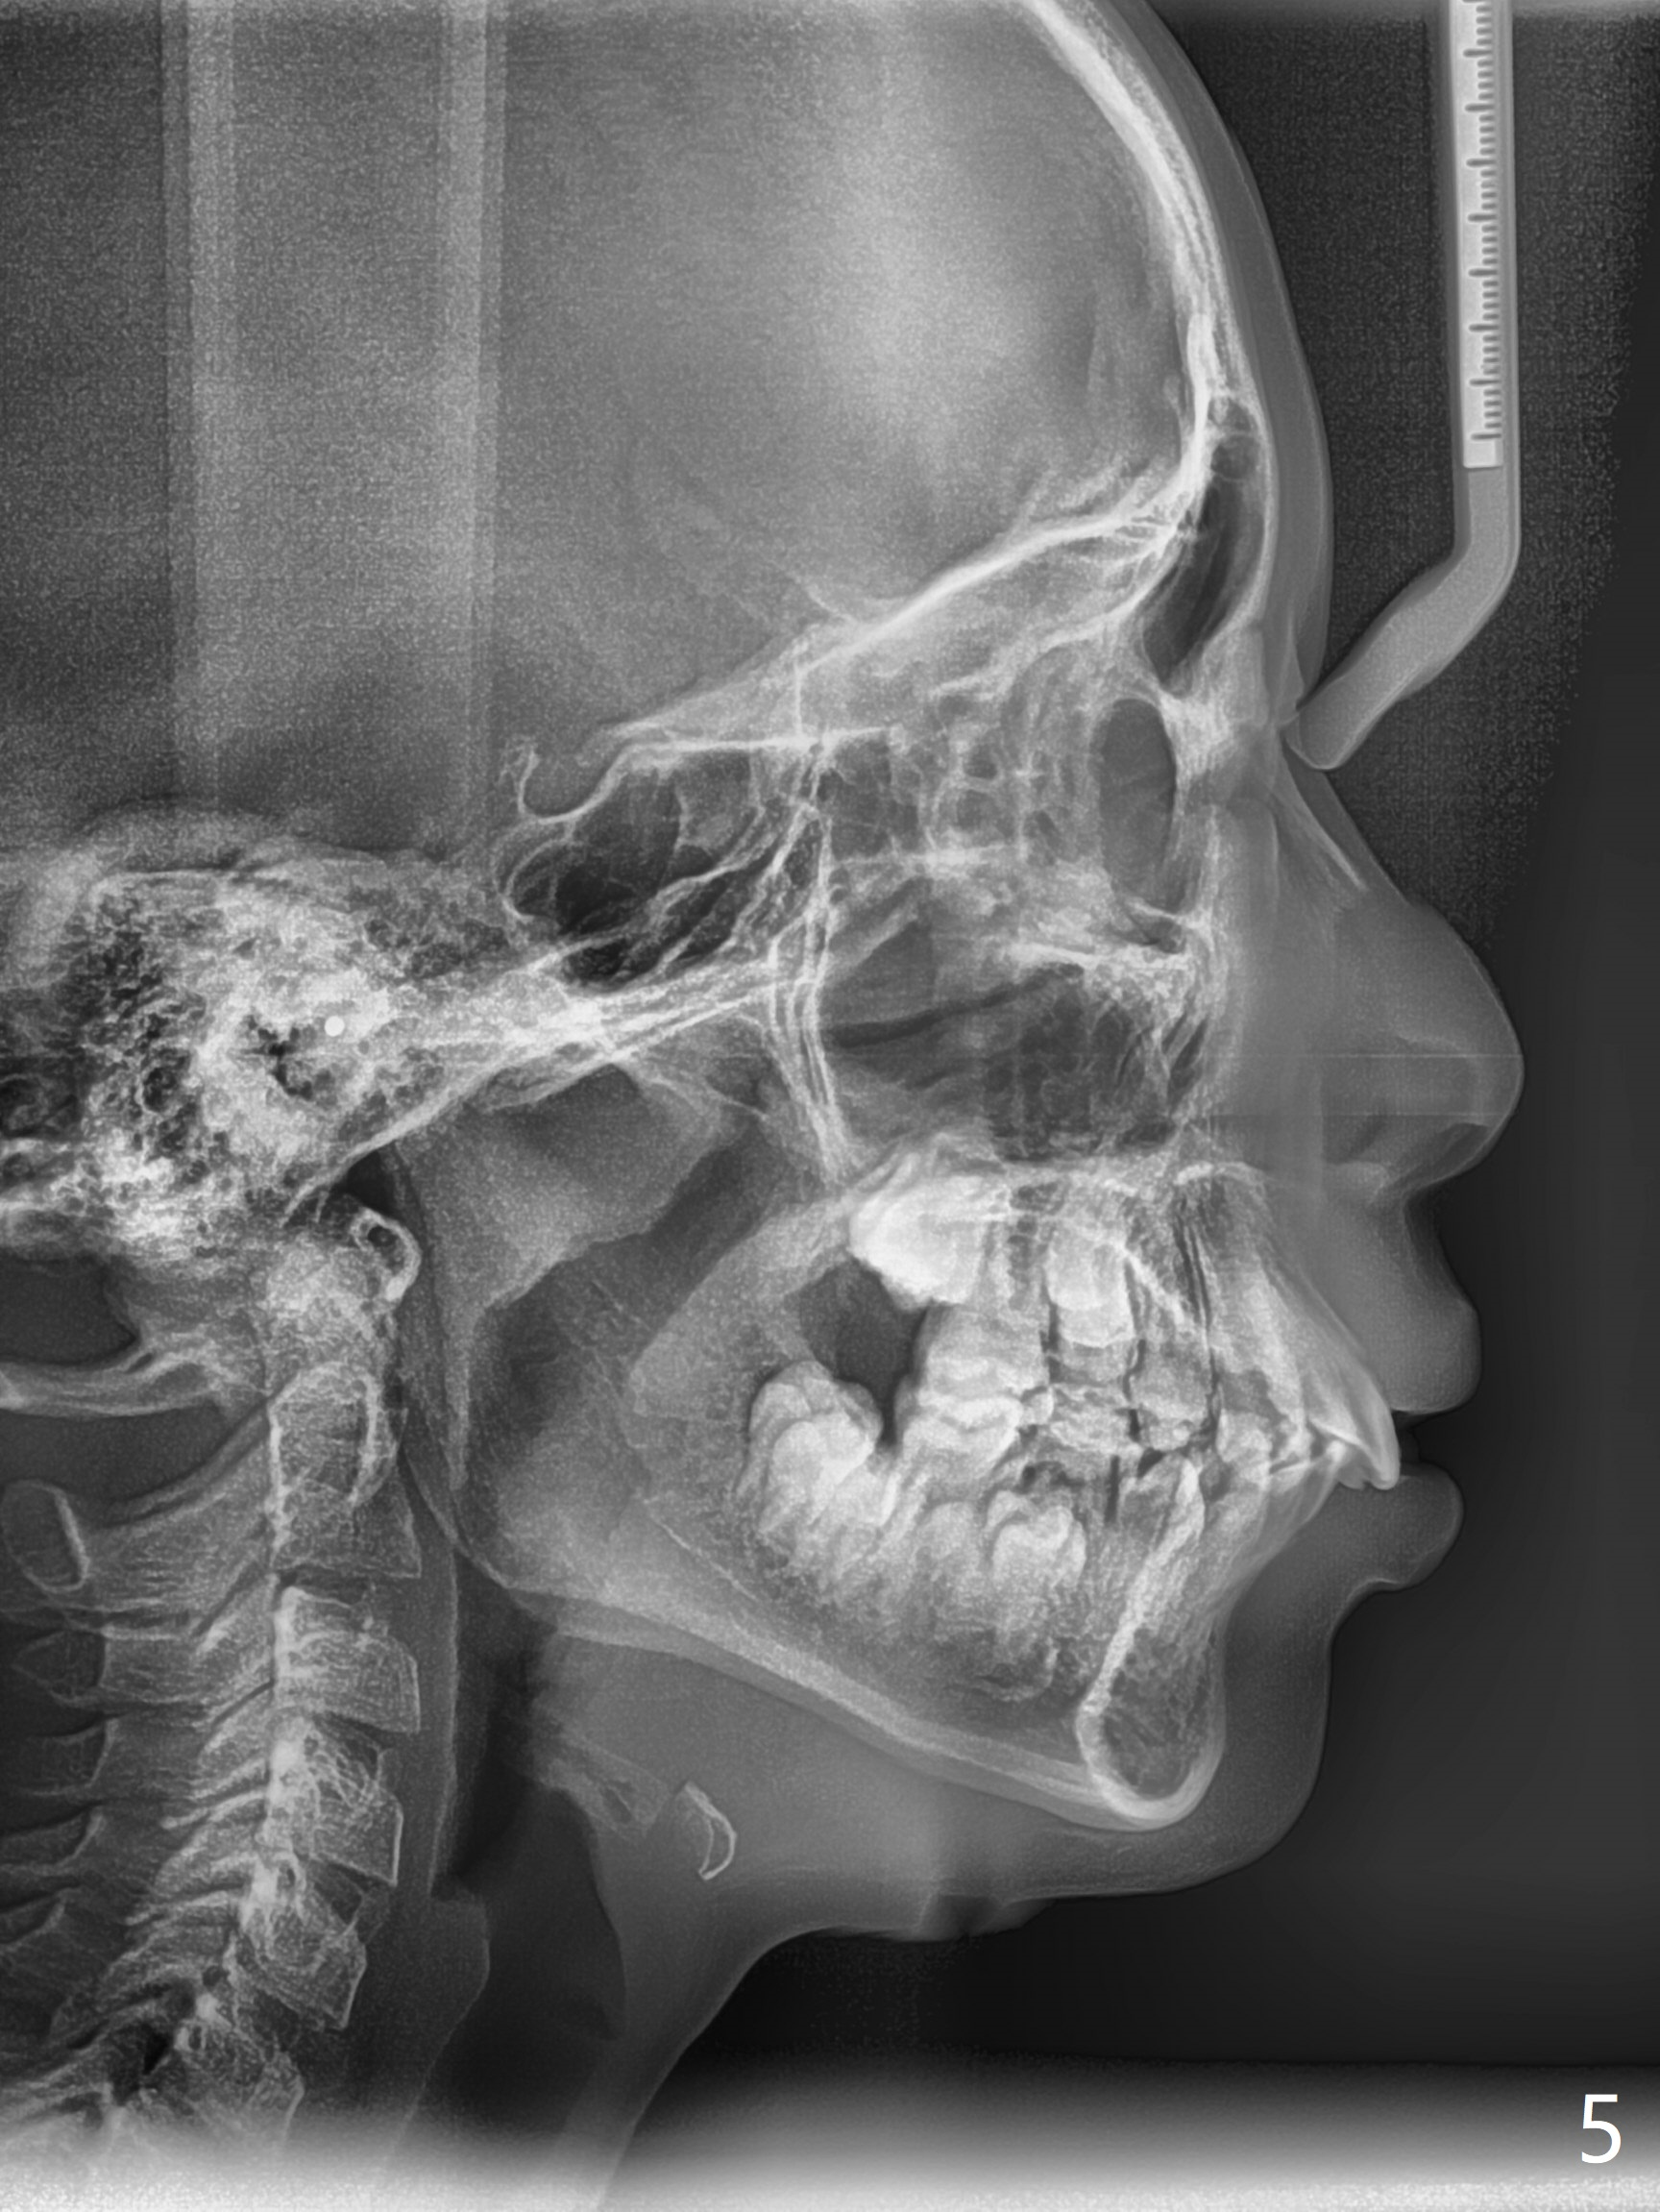

The mother of a 10-year-7-month old man requests treatment for the crowding lower incisors (Fig.14). The canines and molars are Class II by a half of a tooth (Fig.7,9,10,12). The dentition is mixed with E retention (Fig.13,14,16). Orthodontic treatment will start before E exfoliation for alignment and establishment of Class I occlusion as much as possible by distalizing U6s. Fine adjustment for intedigitation will be made when E exfoliate.